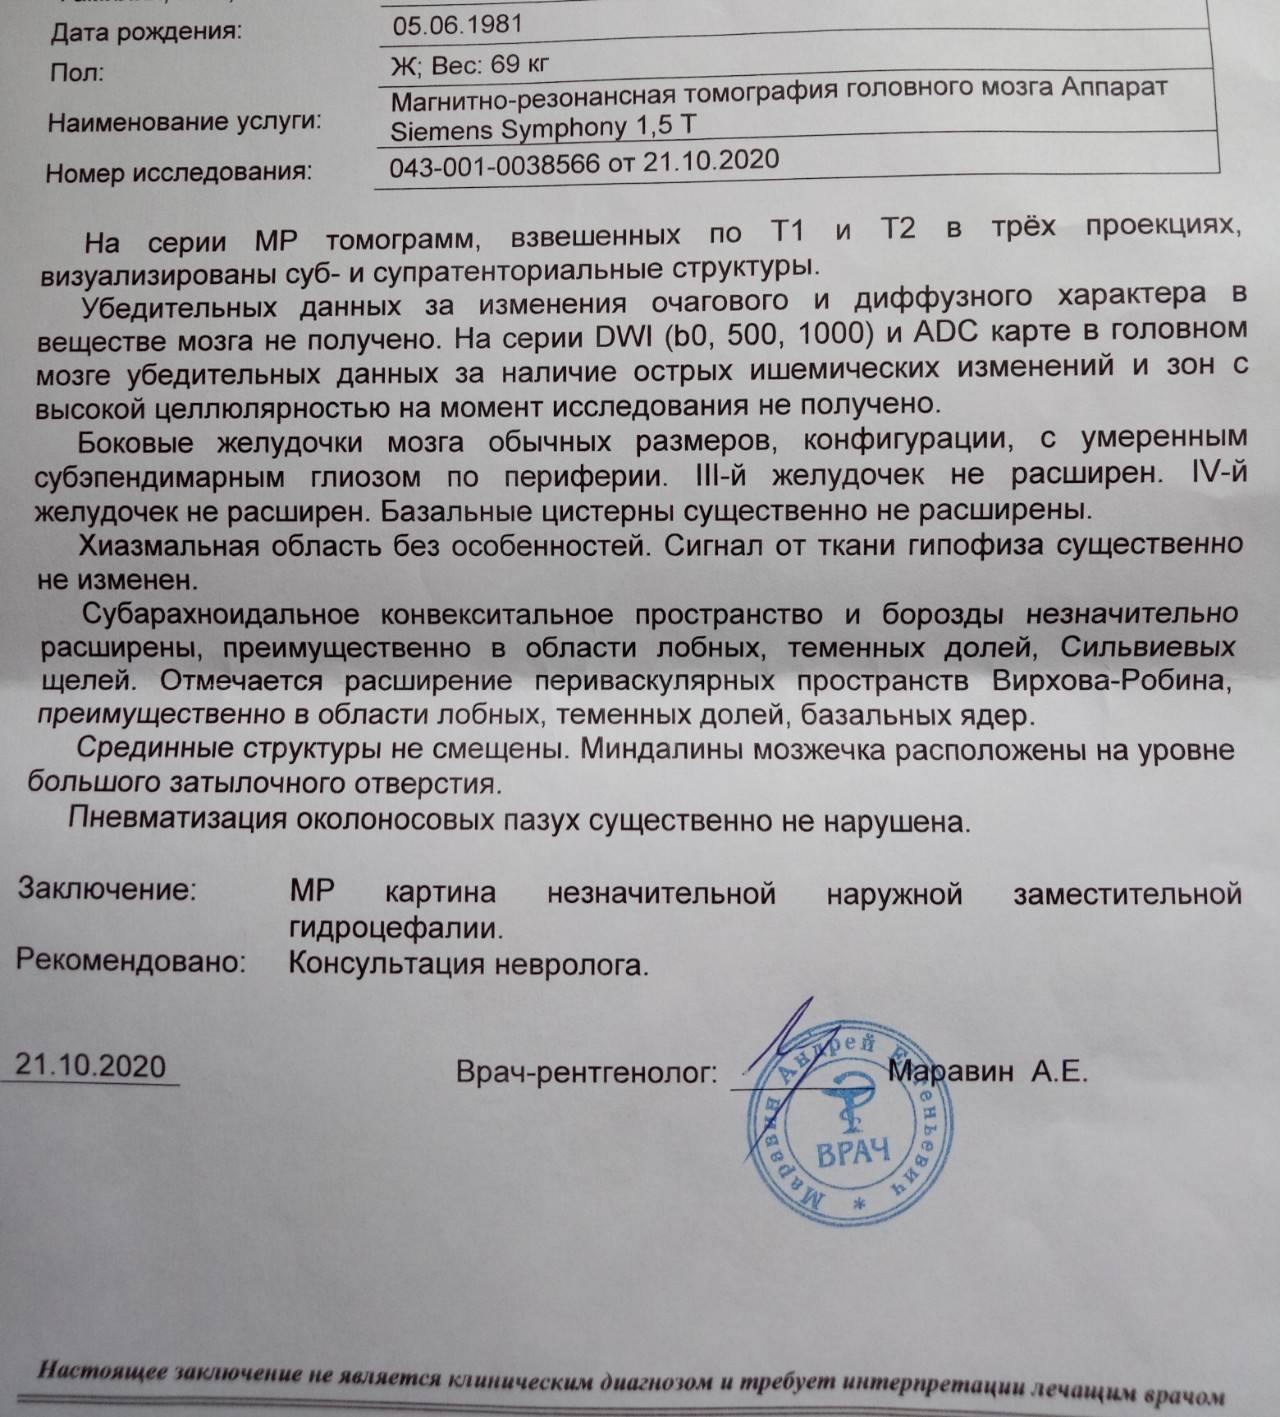

Признаки умеренно выраженной наружная

Признаки умеренно выраженной наружная 113 фото